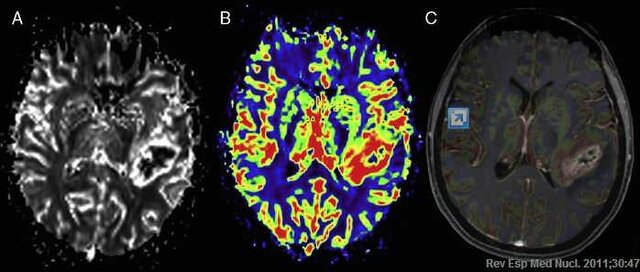

• NEUROIMAGENES

NEUROIMAGENES

Se implementa por medio de rayos x , el cual es la herramienta con mayor implimentacion el actualidad, (TAC),(TEP) (EYETRAKER), (RM)